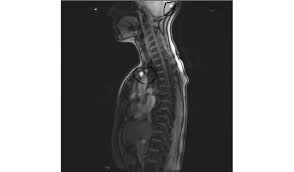

7 Wochen ein MRT der HWS mit der Diagnose Foraminastenose bds cervicaler Bandscheibenschaden Z.

Die Kernspintomographie ist für eine frühzeitige und verlässliche Diagnose von. Jahrelang wurde davon ausgegangen dass sich diese Veränderungen auf die weiße Gehirnsubstanz beschränken. Bei Zysten oder Vernarbungen im Bereich des Gehirns hindeuten. Wenn mehrere vernarbte Stellen größere Herde bilden spricht man von Plaques. Bei dem weißen Punkt rechts im Bild neben der Halswirbelsäule handelt es sich um eine Markierung auf der Haut die den Schmerzpunkt anzeigt. Es handelt sich um eine Schnittbild im coronaren Strahlengang parallel zur Stirn Der weisse Fleck ist ein Anschnitt der Aorta die dort einen Bogen macht. Ich weiß aber wie quälend es ist solange auf die Befundbesprechung zu warten. Ist die Aufnahme von vorne oder von hinten. Die Kernspintomographie ist für eine frühzeitige und verlässliche Diagnose von.

Bei Zysten oder Vernarbungen im Bereich des Gehirns hindeuten. Zur weiteren Differenzierung zwischen den Ursachen der Flecken sind Tests erforderlich die in der Regel durch einen Neurologen durchgeführt werden. Das Rückenmark als Schlüssel zur MS-Diagnostik. MRT der LWS T2 linkes Bild Weiß kann man die Entzündung der Lendenwirbelsäule erkennen da die Bandscheibe durch die Fehlstellung aufgebraucht wurde und nun Knochen auf Knochen reibt und eine Entzündung des Knochens entsteht. Ich habe viele mrt bilder von mir daheim. 7 Wochen ein MRT der HWS mit der Diagnose Foraminastenose bds cervicaler Bandscheibenschaden Z. Ein Computer wandelt diese Signalen in sichtbare Bilder um.